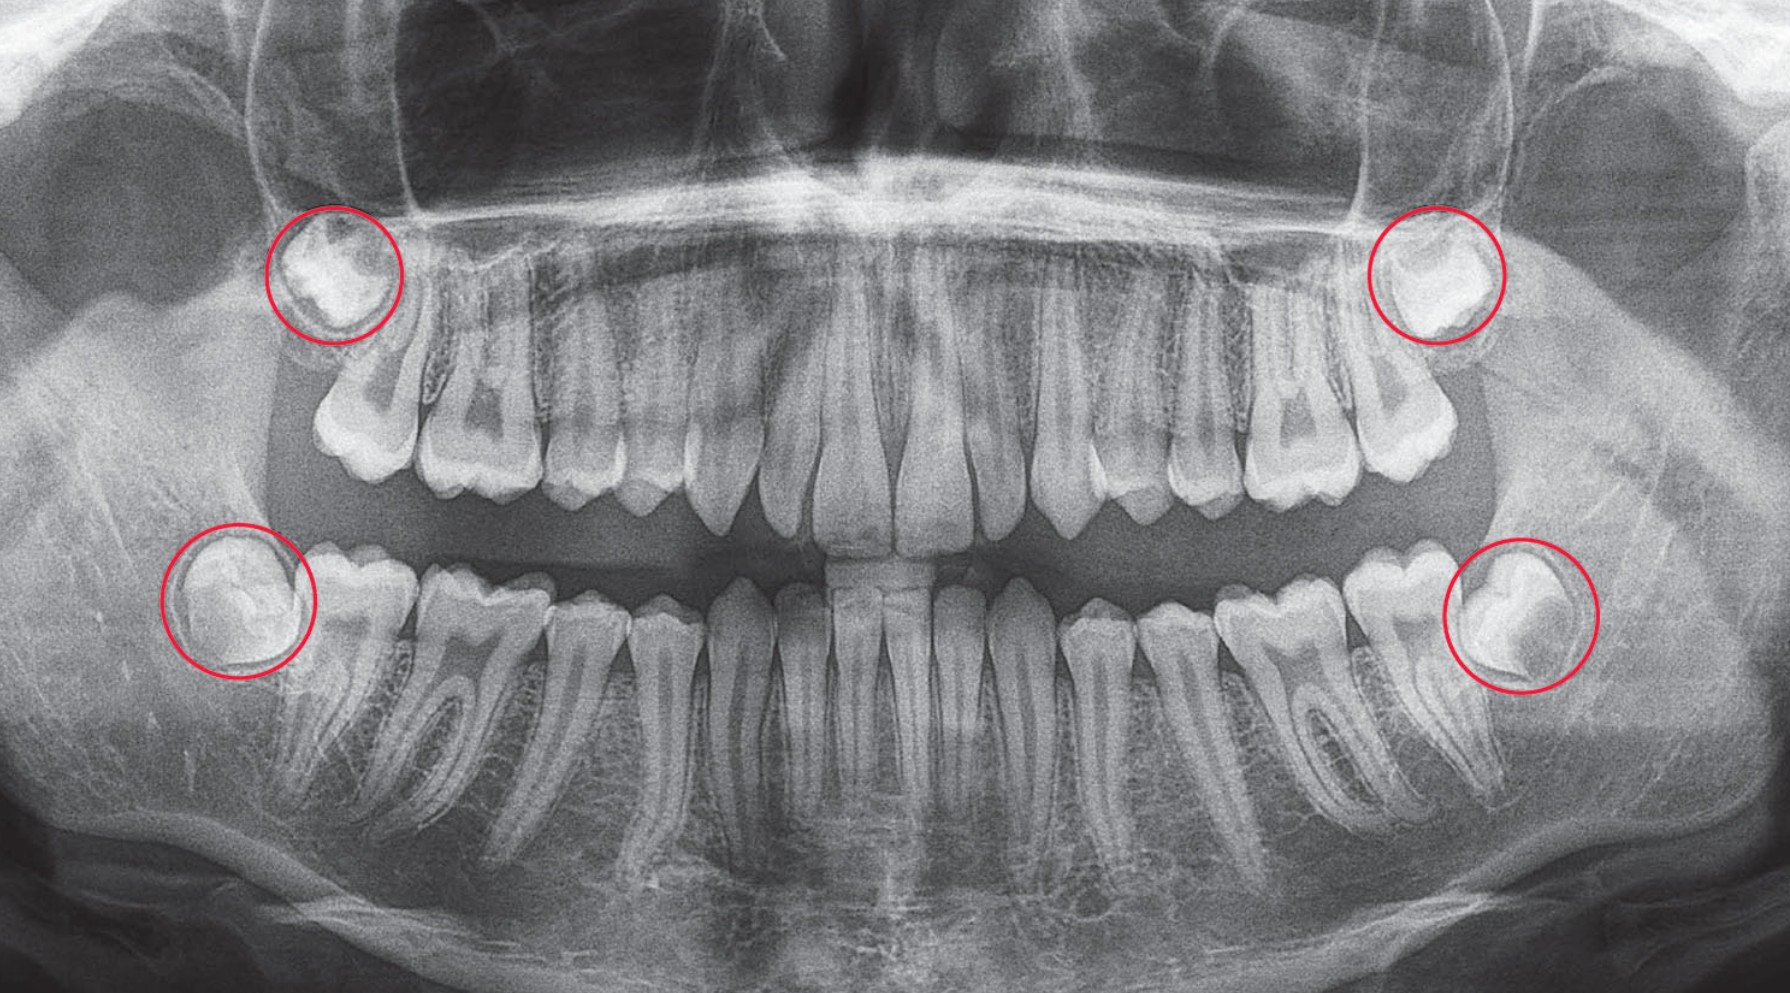

Giai đoạn đầu tiên, răng khôn hình thành trong xương hàm và chỉ có thể thấy trên phim X-quang toàn cảnh. Lúc này, mầm răng nằm sâu dưới nướu, chưa gây cảm giác gì rõ rệt. Khi chân răng bắt đầu phát triển, răng sẽ dịch chuyển dần lên phía trên. Nếu cung hàm đủ chỗ, răng có thể mọc thẳng; nhưng nếu không, nó sẽ nghiêng hoặc đâm vào răng số 7 kế cận.

Khi răng khôn bắt đầu nhú khỏi nướu, đó là giai đoạn “chuyển mình” từ xương ra khoang miệng. Lúc này, một phần thân răng có thể đã xuất hiện, nhưng phần chân răng phía dưới vẫn còn đang hình thành và có khả năng tiến sát dây thần kinh hàm dưới. Chính vì vậy, việc đánh giá qua phim X-quang là vô cùng quan trọng để xác định hướng mọc và độ an toàn nếu cần nhổ bỏ.

- Răng khôn mọc lệch, mọc kẹt hoặc có hướng đâm vào răng số 7 (thường xác định qua phim X-quang).

- Bác sĩ nhận thấy răng khôn có nguy cơ ảnh hưởng đến dây thần kinh, xương hàm hoặc răng kế cận.

- Kết quả phim X-quang toàn cảnh (Panorex) để xác định hướng mọc và vị trí chân răng.

- Mức độ phát triển của chân răng, khoảng cách với dây thần kinh hàm dưới.

- Tình trạng của răng số 7 kế cận, nướu và xương ổ răng.

- Thăm khám và chụp phim 3D Cone Beam: giúp bác sĩ xác định chính xác hướng mọc, chiều sâu và vị trí dây thần kinh.